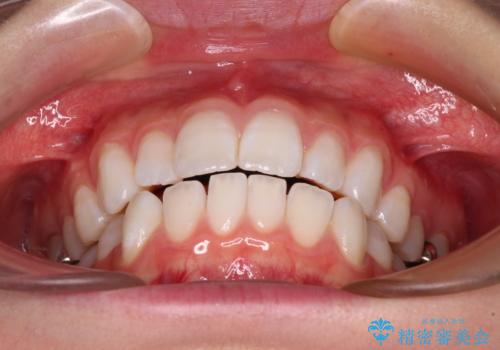

【モニター】口が閉じにくい 膨らんだ口元を抜歯矯正ですっきりと

- 前歯の出っ歯と口元の閉じにくさを気にして来院された患者様です。

口元を積極的に引っ込めるために、上下左右の小臼歯4本を抜歯することとしました。

4本の歯を抜歯したことで、飛び出していた口元が引っ込み、横顔が大きく改善されました。